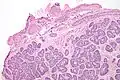

| Micrograph of a Sertoli cell nodule. H&E stain. | |

A Sertoli cell nodule is a benign proliferation of Sertoli cells that arises in association with cryptorchidism (undescended testis).[1] They are not composed of a clonal cell population, i.e. neoplastic; thus, technically, they should not be called an adenoma.[2]

Sertoli cell nodules are unencapsulated nodules that consist of:[2][3][4]

- cells arranged in well-formed tubules (that vaguely resemble immature Sertoli cells), with

- bland hyperchromatic oval/round nuclei that are stratified, and

- may contain eosinophilic (hyaline) blob in lumen (centre).